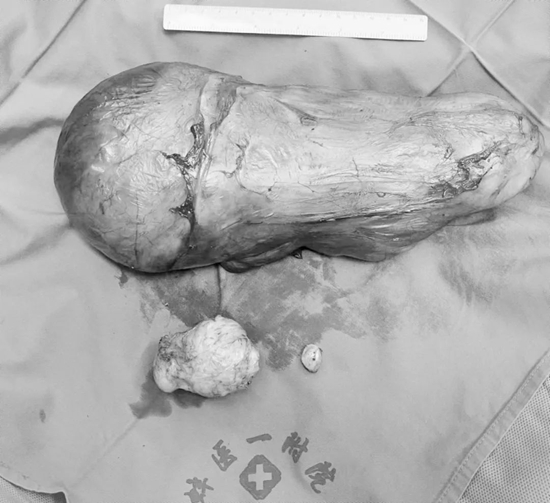

3月24日9點(diǎn),患者被推入手術(shù)室。麻醉科張運(yùn)淳主任醫(yī)師完成留置深靜脈置管、有創(chuàng)動(dòng)脈導(dǎo)管后立即進(jìn)行誘導(dǎo)麻醉、氣管插管,各種搶救藥品保證呼吸循環(huán)功能。術(shù)中周新社主任醫(yī)師及嚴(yán)曉波副主任醫(yī)師仔細(xì)分離瘤體保護(hù)周圍血管神經(jīng),見腫瘤沿閉孔向臀部生長(zhǎng),腫瘤組織與膀胱后壁粘連,泌尿外科代昌遠(yuǎn)副主任醫(yī)師仔細(xì)分離腫瘤粘連組織,避免膀胱損傷,術(shù)中沿前后切口分別分離后,完整取出大小約30 cmx15 cmx10 cm腫瘤組織;盆腔腫瘤取出后,在婦科郭祥瑞醫(yī)師協(xié)同下行子宮肌瘤切除術(shù),手術(shù)時(shí)長(zhǎng)3.5 h,比預(yù)計(jì)時(shí)長(zhǎng)縮短2 h,術(shù)中出血400 ml,考慮手術(shù)創(chuàng)傷較大,患者既往一般情況差,術(shù)后轉(zhuǎn)至重癥監(jiān)護(hù)室進(jìn)一步治療。